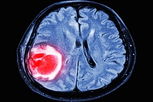

Ter calcificação no cérebro é perigoso?

A calcificação no cérebro nem sempre é grave, podendo surgir naturalmente na medida em que a pessoa envelhece. No entanto, em alguns casos pode indicar problemas mais sérios, como infecções, doenças dos vasos sanguíneos, síndromes genéticas, alterações hormonais ou tumores.

No entanto, especialmente quando devido ao envelhecimento, normalmente não causam sintomas, sendo identificadas por acaso ao se realizar exames de imagem, como tomografia computadorizada ou ressonância magnética.